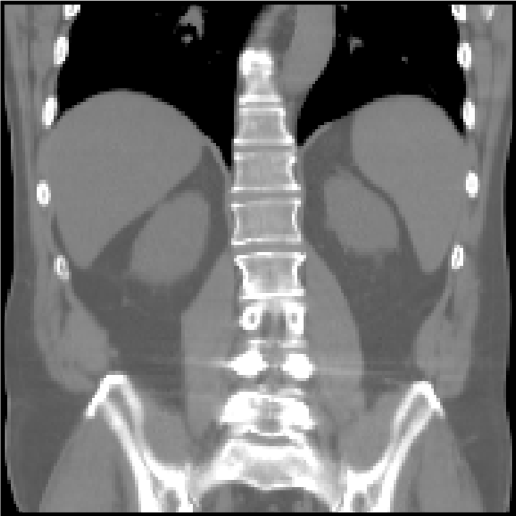

Abdomen CT-CT

This task tackles inter-patient registration of abdominal CT scans, which enables statistical modelling of variations of organs for abnormality detection, and can provide a canonical atlas space for further investigations. The dataset contains 50 abdominal CT scans (30/20 for training/testing) with 13 manually labelled anatomical structures: spleen, right/left kidney, gall bladder, esophagus, liver, stomach, aorta, inferior vena cava, portal and splenic vein, pancreas and left/right adrenal gland. Data acquisition and annotation protocols are detailed in [12]. The images were registered affinely in a groupwise manner and resampled to the same voxel resolution and spatial dimensions (192×160×256192160256192{\times}160{\times}256).